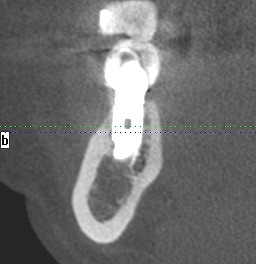

機能時のCTになります